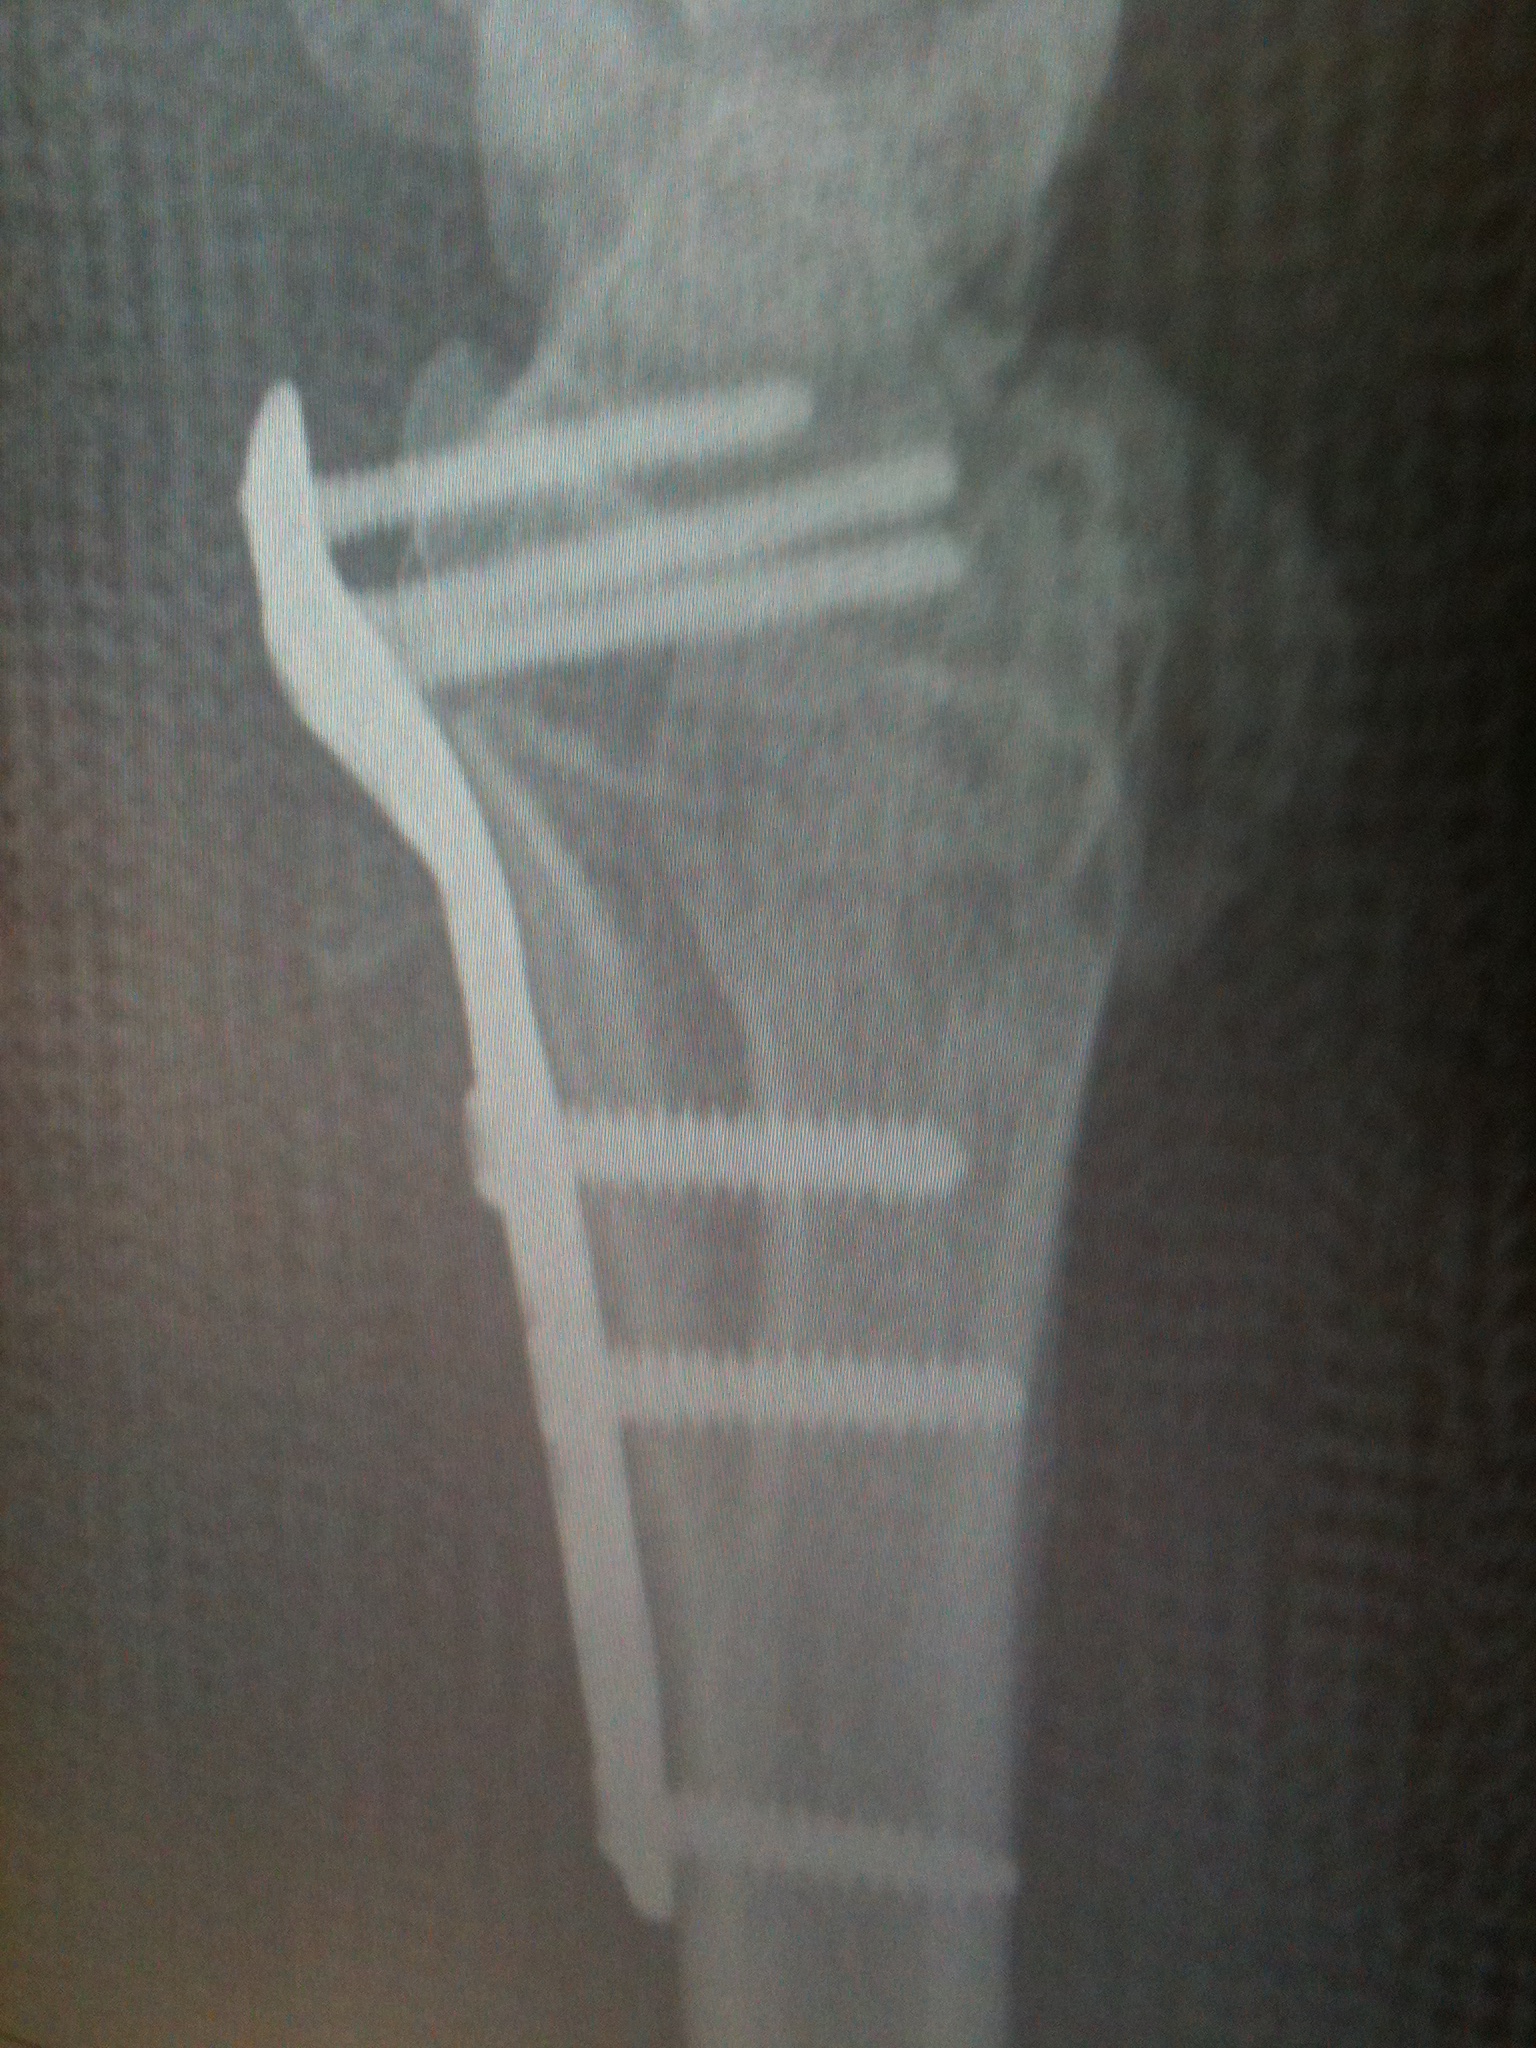

Metal Plate In Wrist Distal radius fractures can be reset either with surgery (open reduction) or without it (closed reduction). in 332 patients surveyed, most hardware removals were performed at the ankle joint (21 %) followed by the wrist (15. learn about the common procedure of open reduction internal fixation (orif) to repair a fractured wrist with a metal plate and screws. Find out how to prevent complications and restore wrist function with nonsurgical or surgical options. learn about the common types, causes and diagnosis of distal radius fractures, a break in the larger bone of the forearm near the wrist. the metal plate and screws usually stay in for life and are not routinely removed. It can be classified as colles or smith depending on the angle of. Motion and light use of the wrist are. wrist surgery can be done to fix problems like arthritis, fractures, and carpal tunnel. Surgical techniques and recovery time. a distal radius fracture is a break near the wrist caused by falling on an outstretched or flexed hand. learn about the causes, symptoms, diagnosis, and treatment of distal radius fractures, which are very common breaks of the forearm bone near the wrist. However, if the metal becomes infected or. learn about the reasons, benefits, and risks of removing metal plates, screws, or rods after orthopedic surgery. an increasingly popular treatment approach to a distal radius fracture is to surgically implant plates, screws, or pins to hold the bone fragments in place. what is an orif (open reduction internal fixation)?

Distal Radius Fracture Raleigh Hand Surgery — Joseph J. Schreiber, MD Metal Plate In Wrist If a wrist is broken in such a way that the ends of the fracture do not meet. mr kemble wang has recommended that the metalware (most commonly plates and screws) removed from your wrist. Find out how hss experts. what is an orif (open reduction internal fixation)? the metal plate and screws allow people to start. Metal Plate In Wrist.

Arthrex Wrist Spanning Plate Technique Metal Plate In Wrist like any procedure though, surgery for wrist fractures does carry some associated risks and realistic expectations must be based. mr kemble wang has recommended that the metalware (most commonly plates and screws) removed from your wrist. your surgeon will repair your broken bones and insert a metal plate and screws into your wrist to hold it together.. Metal Plate In Wrist.

Broken Wrist Plate and Screws YouTube Metal Plate In Wrist learn about the common procedure of open reduction internal fixation (orif) to repair a fractured wrist with a metal plate and screws. Find out how a distal radius fracture. Recovery time for surgery is longer. Distal radius fractures can be reset either with surgery (open reduction) or without it (closed reduction). your surgeon will repair your broken bones. Metal Plate In Wrist.

Fracture Fixation A Gallery C25 Metal Plate In Wrist in 332 patients surveyed, most hardware removals were performed at the ankle joint (21 %) followed by the wrist (15. learn about the causes, symptoms, diagnosis, and treatment of distal radius fractures, which are very common breaks of the forearm bone near the wrist. If a wrist is broken in such a way that the ends of the. Metal Plate In Wrist.

xray of arm, broken arm, plate fixation, titanium plate, fracture of Metal Plate In Wrist the metal plate and screws allow people to start using the wrist earlier. Find out how a distal radius fracture. in 332 patients surveyed, most hardware removals were performed at the ankle joint (21 %) followed by the wrist (15. Find out how to manage. mr kemble wang has recommended that the metalware (most commonly plates and. Metal Plate In Wrist.

Titanium plate for distal radial fractures Metal Plate In Wrist learn about the common procedure of open reduction internal fixation (orif) to repair a fractured wrist with a metal plate and screws. Find out how to prevent complications and restore wrist function with nonsurgical or surgical options. an increasingly popular treatment approach to a distal radius fracture is to surgically implant plates, screws, or pins to hold the. Metal Plate In Wrist.